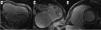

Primary right ventricular disease was the most likely hypothesis and CMR was performed, revealing severe dilation of the right atrium (91×72 mm) and right ventricle (end-diastolic volume 355 ml, 207.9 ml/m2), an extremely thin-walled RV with almost complete absence of the right ventricular free wall myocardium, a paucity of apical trabeculations and impaired systolic function (ejection fraction [EF] 25%) (Figure 2). The left ventricle was dilated with normal wall thickness and an EF of 41%. An ASD measuring over 30 mm was identified and late gadolinium enhancement was observed in the right ventricle and right atrium walls (Figure 3). These findings were compatible with Uhl's anomaly.

Cardiovascular magnetic resonance: Steady-state free precession imaging documenting severe dilation of the right atrium and right ventricle, an extremely thin-walled right ventricle with almost complete absence of the right ventricular free wall myocardium, with a paucity of apical trabeculations, in a four-chamber view in diastole (A) and systole (B), and coronal view (C). An atrial septal defect measuring over 30 mm was also identified.